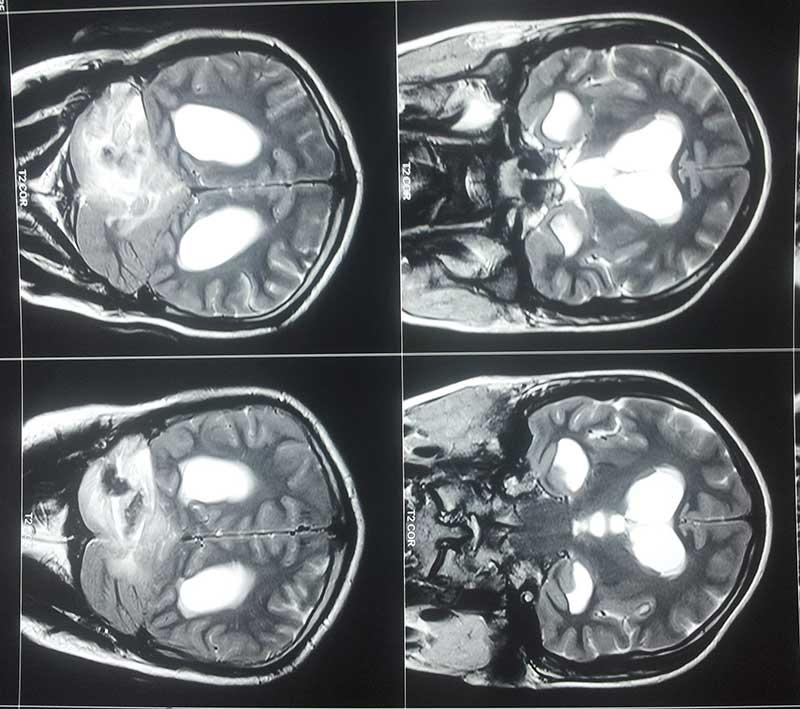

Obstructive Hydrocephalus 2 Pre Op Mri

Preop Mri 1